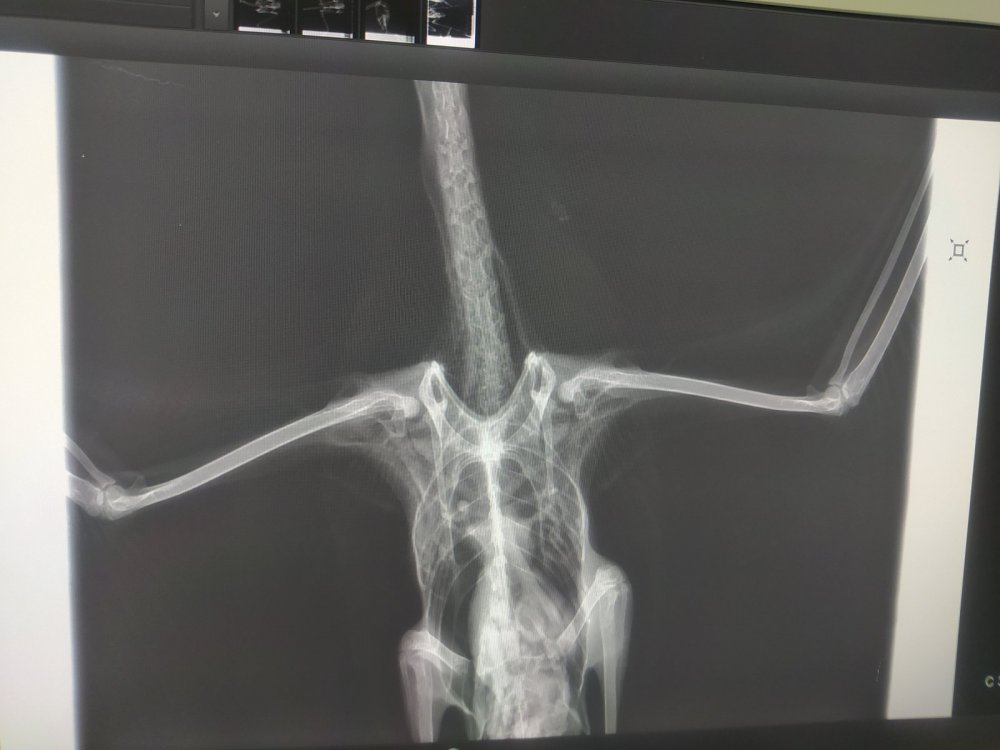

Четрые дня назад на участке нашла птицу, убегает, клюется, самостоятельно ест и пьет. В первый день была покормлена 2 варёными яйцами, все остальные дни только размороженная рыба. Днём гуляет по участку, на ночь убираю в картонную коробку. Думаю это серебристая или средиземноморская чайка. Вес около двух кг. На рентгене переломов не замечено

По чайкам тоже не спец. Но левое крыло не рабочее.от слова совсем.

Короче, с костями птицы все было нормально, оба крыла рабочие, но.. Вот эта вот крохотная металлическая проволока проигнорированная мной на рентгене как артефакт её и убила(

Распорот кишечник, гнойный перетонит, тромб в сердце (скорее всего посмертный)